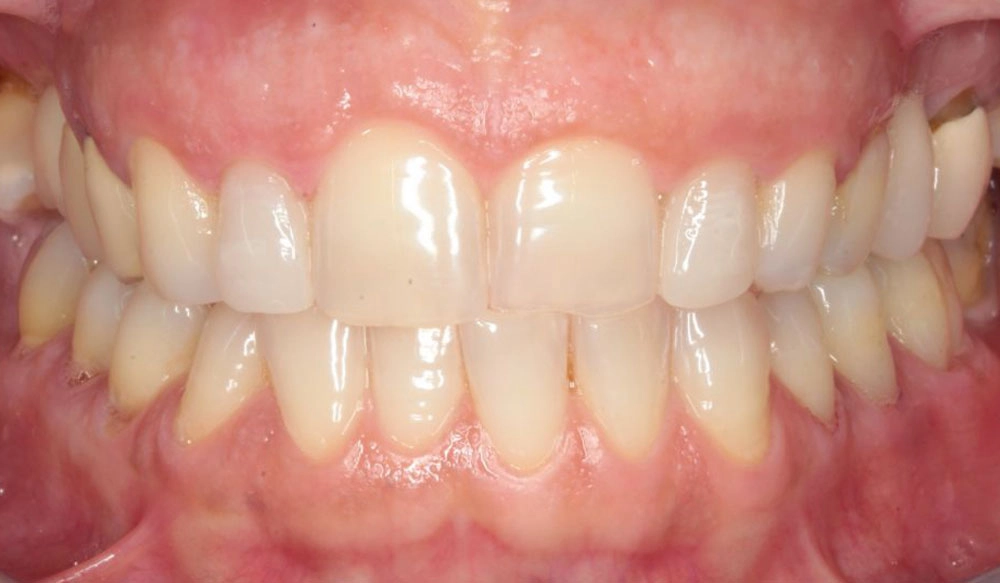

Chen chúc

Chen chúc là tình trạng có sự chênh lệch giữa kích thước răng và không gian có sẵn để sắp xếp răng trên cung răng.

Thông tin bệnh nhân:

Tuổi: 17

Giới tính: nữ

Lựa chọn điều trị Invisalign: Invisalign Comprehensive

Tổng thời gian điều trị:

29 tháng